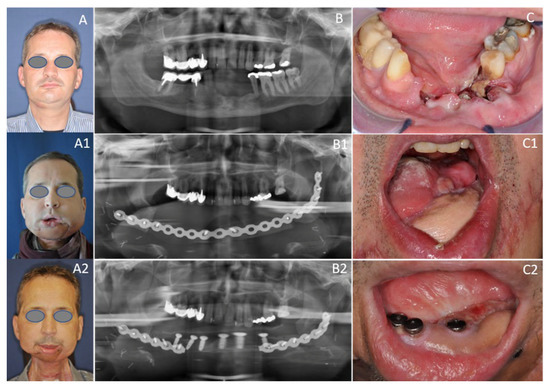

Patients received fixed dentures in the edentulous mandible supported by four implants placed in the interforaminal region. Oral rehabilitation based on osseointegrated dental implants can often be difficult, as head and neck cancer patients show disability, facial deformity, and impaired speech after mandibular resection and reconstruction, and suffer from side effects of radiotherapy [37]. Dental implants are central to the sustainability of oral health and prosthetic rehabilitation, as the use of implant-retained prostheses facilitate chewing and speaking, and may provide aesthetic improvement [37]. Implant survival differs significantly across a variety of bone types, both resected and non-resected. According to the literature, implant survival was highest for implants placed into vascularized bone grafts, such as SFFs (100%), followed by FFFs (83%), while it was lowest in DCIA flaps (76%) [38]. This is in line with the findings of the present study that revealed remarkably high (100%) survival for implants placed into SFFs (n = 25). This substantial implant survival rate could be due to more cortical bone, as peri-implant bone resorption increases with lower cortical bone quality [38]. This confirmed that the lateral border of the scapula offers good bone quality and reliable osseointegration [39,40,41], contrary to preliminary reports [34]. Implant success, however, is usually reported to be lower than implant survival in the literature [37]. Furthermore, the comparison of implant success is difficult, as there are many different definitions in previous research and different implant systems used in oncologic patients [37]. In addition, the present study did not investigate radiographic peri-implant bone loss [37]. Interestingly, in the present sample, 22.7% of patients had dental rehabilitation (Figure 6) after discharge. There is evidence in the literature to support the observation that the use of dental implants in oncologic patients was relatively low, although dental rehabilitation was beneficial for patients [34,37,38].

Figure 6.

Fifty-four-year-old male patient with OCSCC reconstructed with the subscapular system free flap. (A) Preoperative status with perforating tumor on the right side; (B) Preoperative dental panoramic radiograph with large mandibular defect; (C) Preoperative clinical view with large OCSCC of the alveolar crest; (A1) Postoperative frontal view 10 days postoperatively; (B1) Postoperative dental panoramic radiograph displaying reconstructed mandible after insertion of the SFF. (C1) Postoperative clinical view enorally depicting the skin graft after composite mandible reconstruction with the SFF; (A2) Postoperative frontal view two years postoperatively; (B2) Postoperative dental panoramic radiograph displaying the mandible after insertion of implants; (C2) Postoperative clinical view enorally with placed implants.